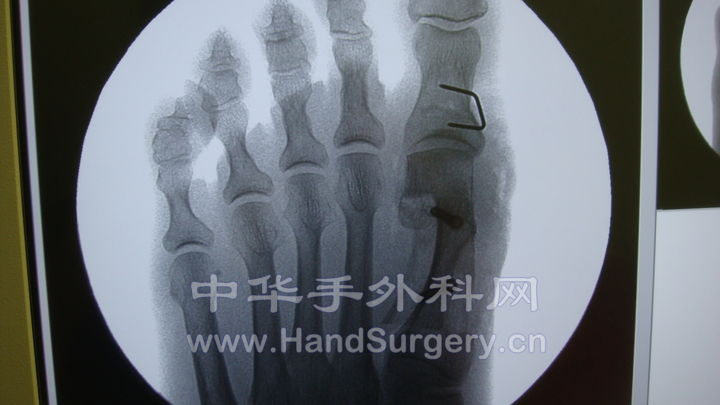

这是一个拇外翻的线片。scarf+Akin术前,术后。

chevron截骨